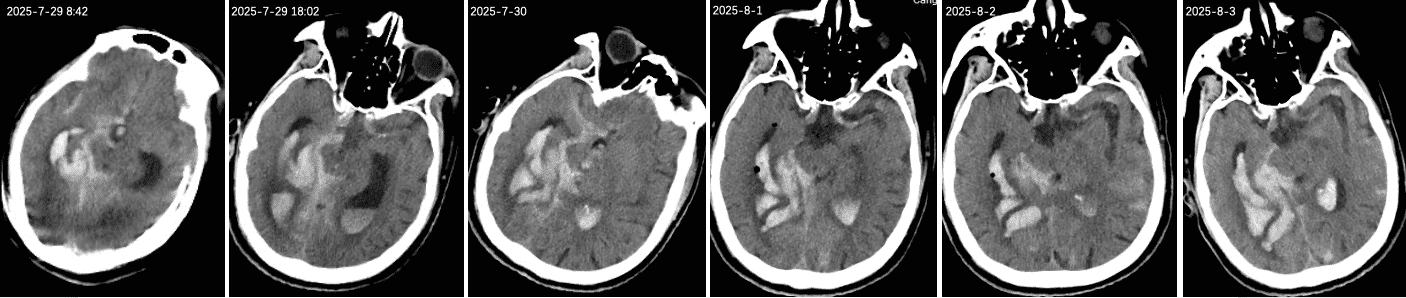

头CT:右侧侧脑室见片状高密度影,脑室内见多发不规则高密度影。双侧大脑半球脑沟内高密度影,额部颅板下见积气影。小脑、右顶叶、双侧额叶、放射冠区、基底节区见半片状低密度影,局部近液体密度影;脑室及脑池系统扩张。双侧脑沟裂增宽、加深,中线结构居中。

1、入院后联系神经外科,鉴于出血量大,征得家属同意后行颅内出血置管引流术,间断引流血性液体,复查CT提示出血减轻,意识也曾一度清醒,示意肢体

可简单活动;

2、8月3日患者意识成昏迷状态,复查CT提示再次出血,急诊ICU告知病情加重预后不良,家属经商议后放弃治疗。三、初步诊断

PS:复盘患者CT情况,颅内出血大部分集中在右侧颞叶,累及中脑环池,且破入侧脑室,考虑患者存在后交通动脉瘤可能性大。